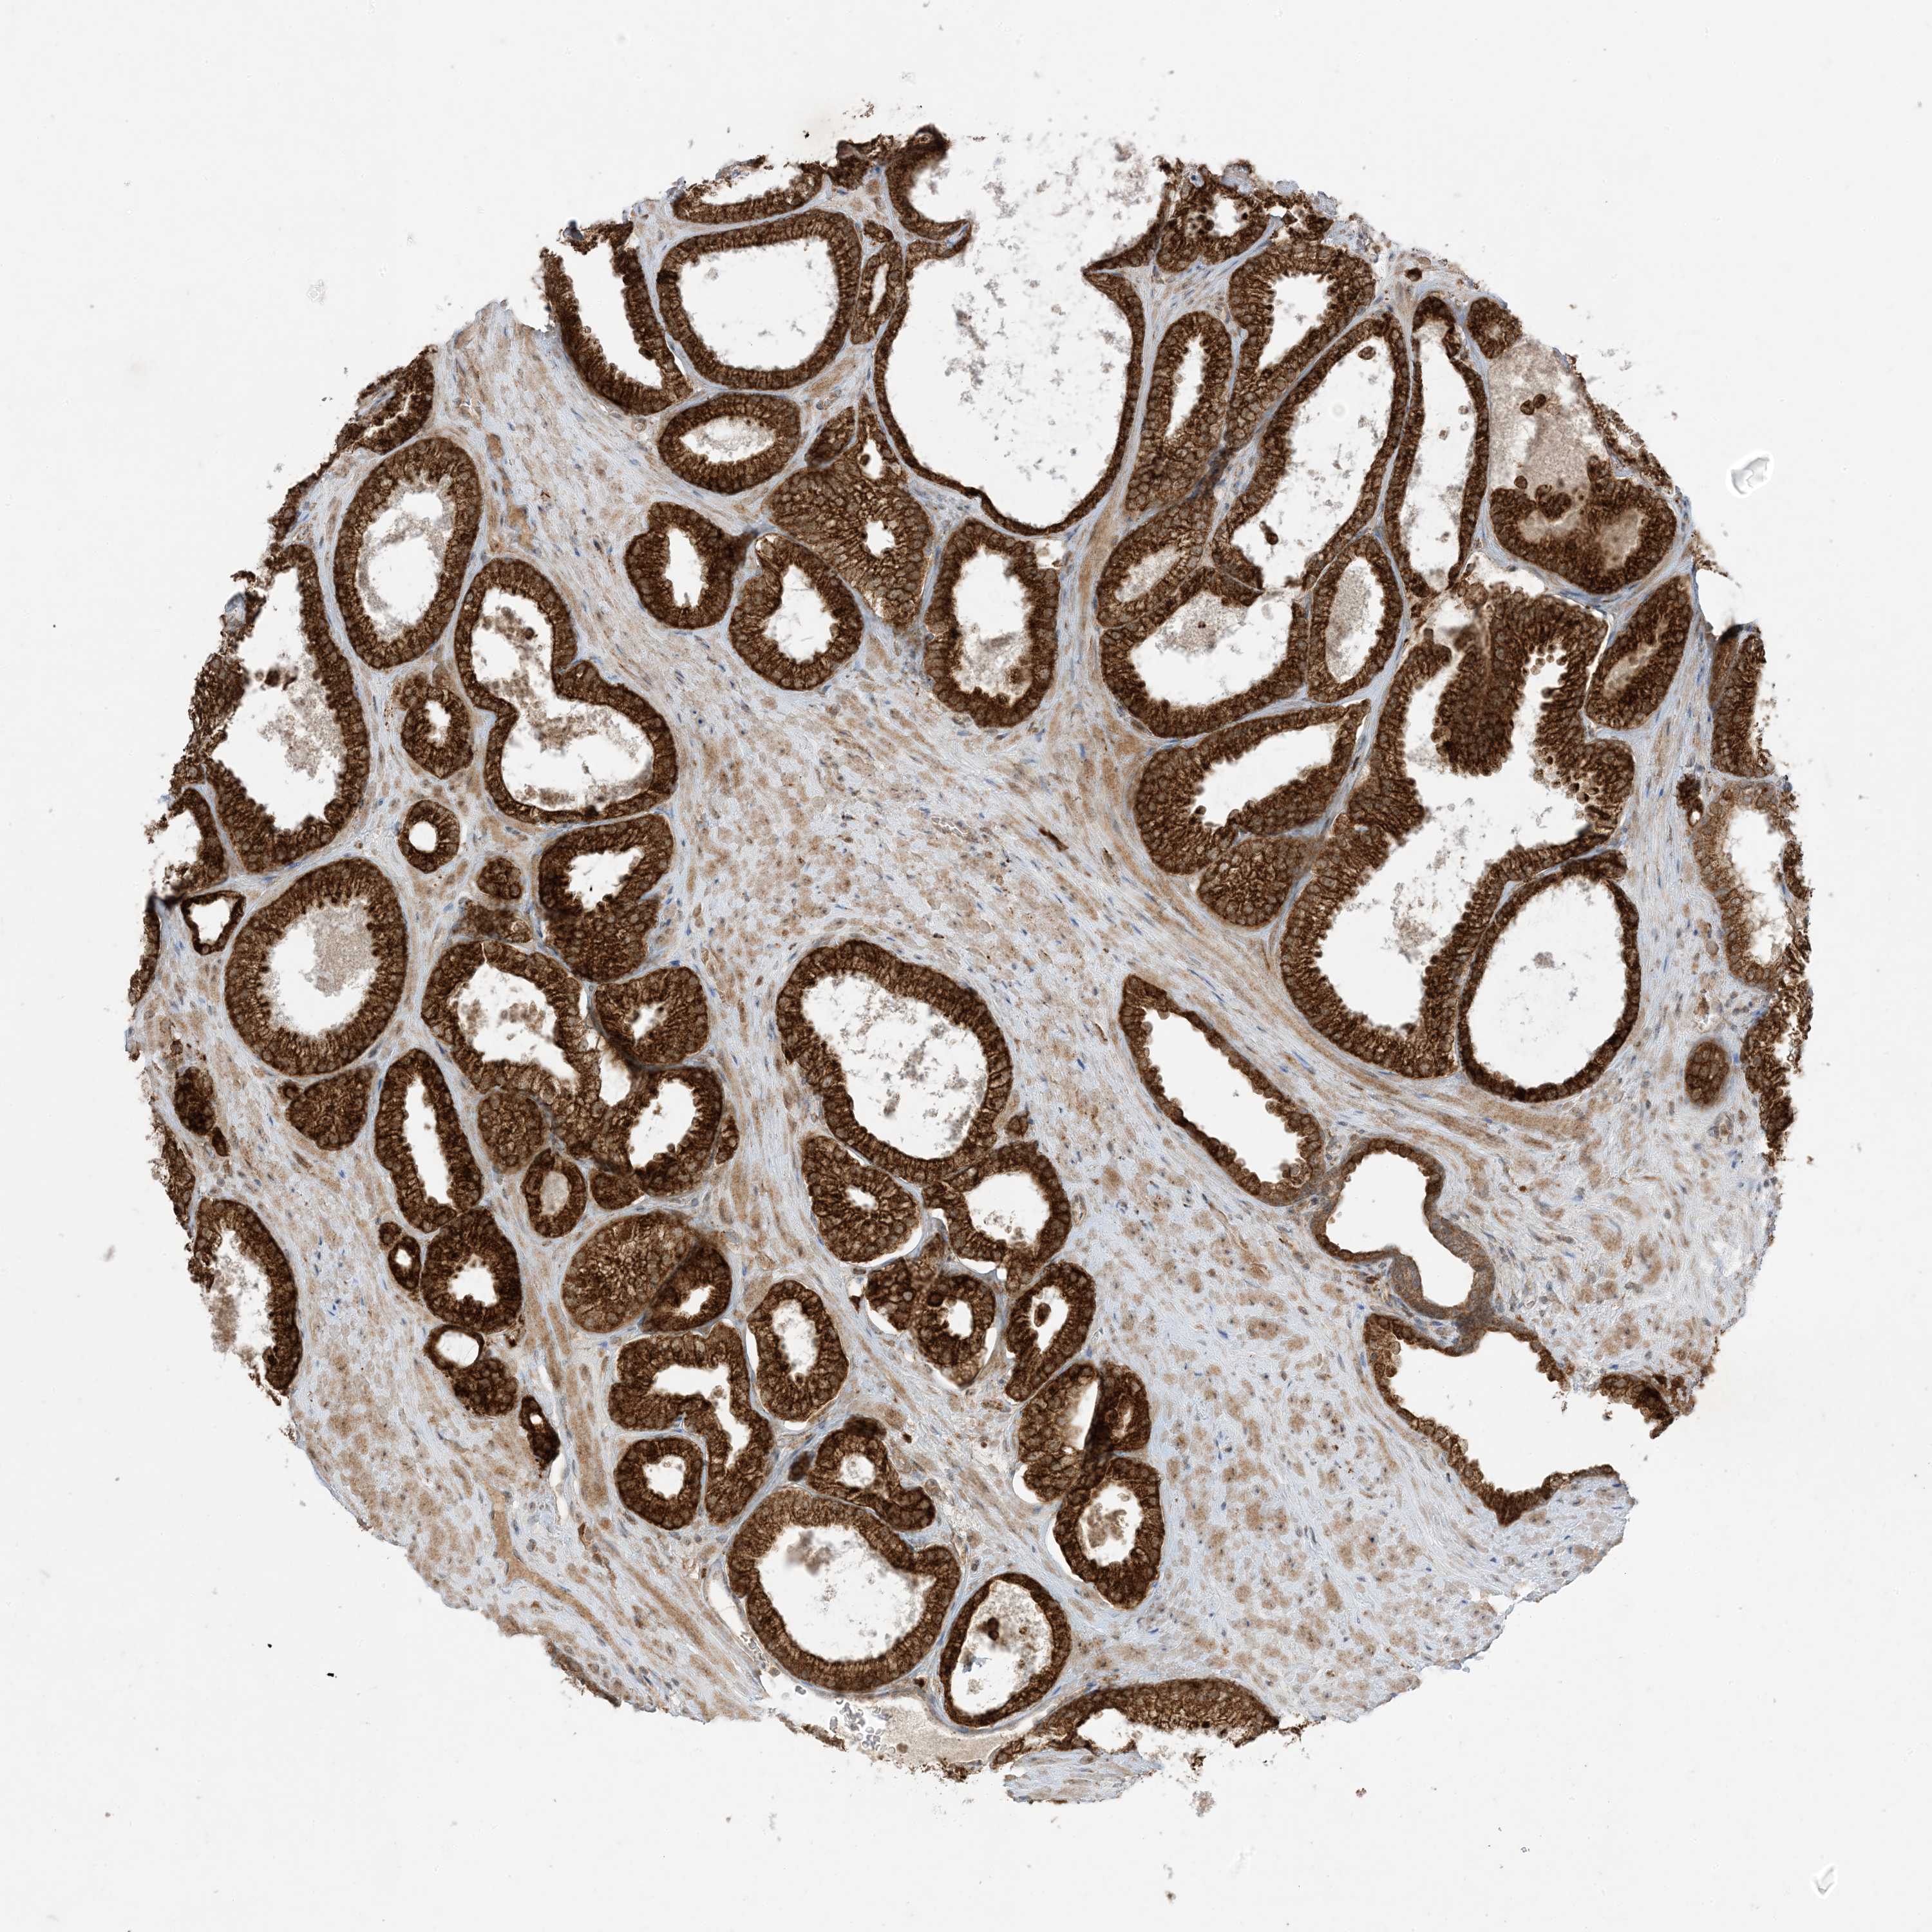

PROSTATE CANCER - Protein expressioni

A mouse-over function shows sample information and annotation data. Click on an image to view it in a full screen mode. Samples can be filtered based on level of antibody staining by selecting one or several of the following categories: high, medium, low and not detected. The assay and annotation is described here.

Note that samples used for immunohistochemistry by the Human Protein Atlas do not correspond to samples in the TCGA dataset.

Antibody stainingi

Antibody staining in the annotated cell types in the current human tissue is reported as not detected, low, medium, or high, based on conventional immunohistochemistry profiling in selected tissues. This score is based on the combination of the staining intensity and fraction of stained cells.

Each image is clickable and will lead to virtual microscopy that enables deeper exploration of all samples and also displays staining intensity scores, fraction scores and subcellular localization as well as patient and tissue information for each sample.

Antibody HPA001536

Antibody CAB035996

Staining

High

Medium

Low

Not detected

Intensity

Strong

Moderate

Weak

Negative

Quantity

>75%

75%-25%

<25%

None

Location

Nuclear

Cytoplasmic/membranous

Cytoplasmic/membranous,nuclear

Adenocarcinoma, Medium grade

Adenocarcinoma, High grade

Adenocarcinoma, Low grade